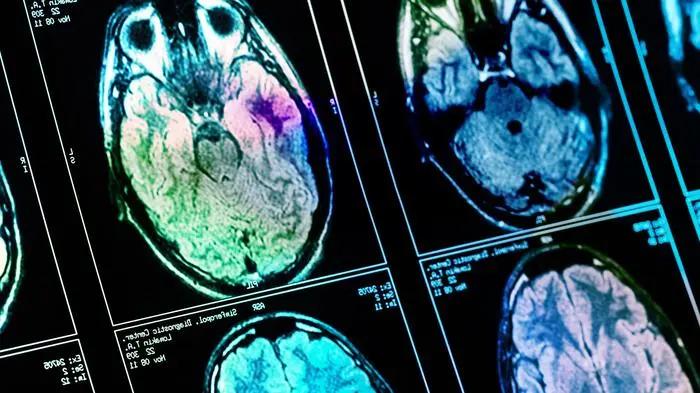

Veränderungen an Hirnstruktur

Wie Covid-19 das Gehirn schädigt

Wie bei so vielen gesundheitlichen Folgen von Covid-19 ist auch hier die überschießende Reaktion des Immunsystems die Ursache. Diese kann die Blut-Hirn-Schranke beeinträchtigen.